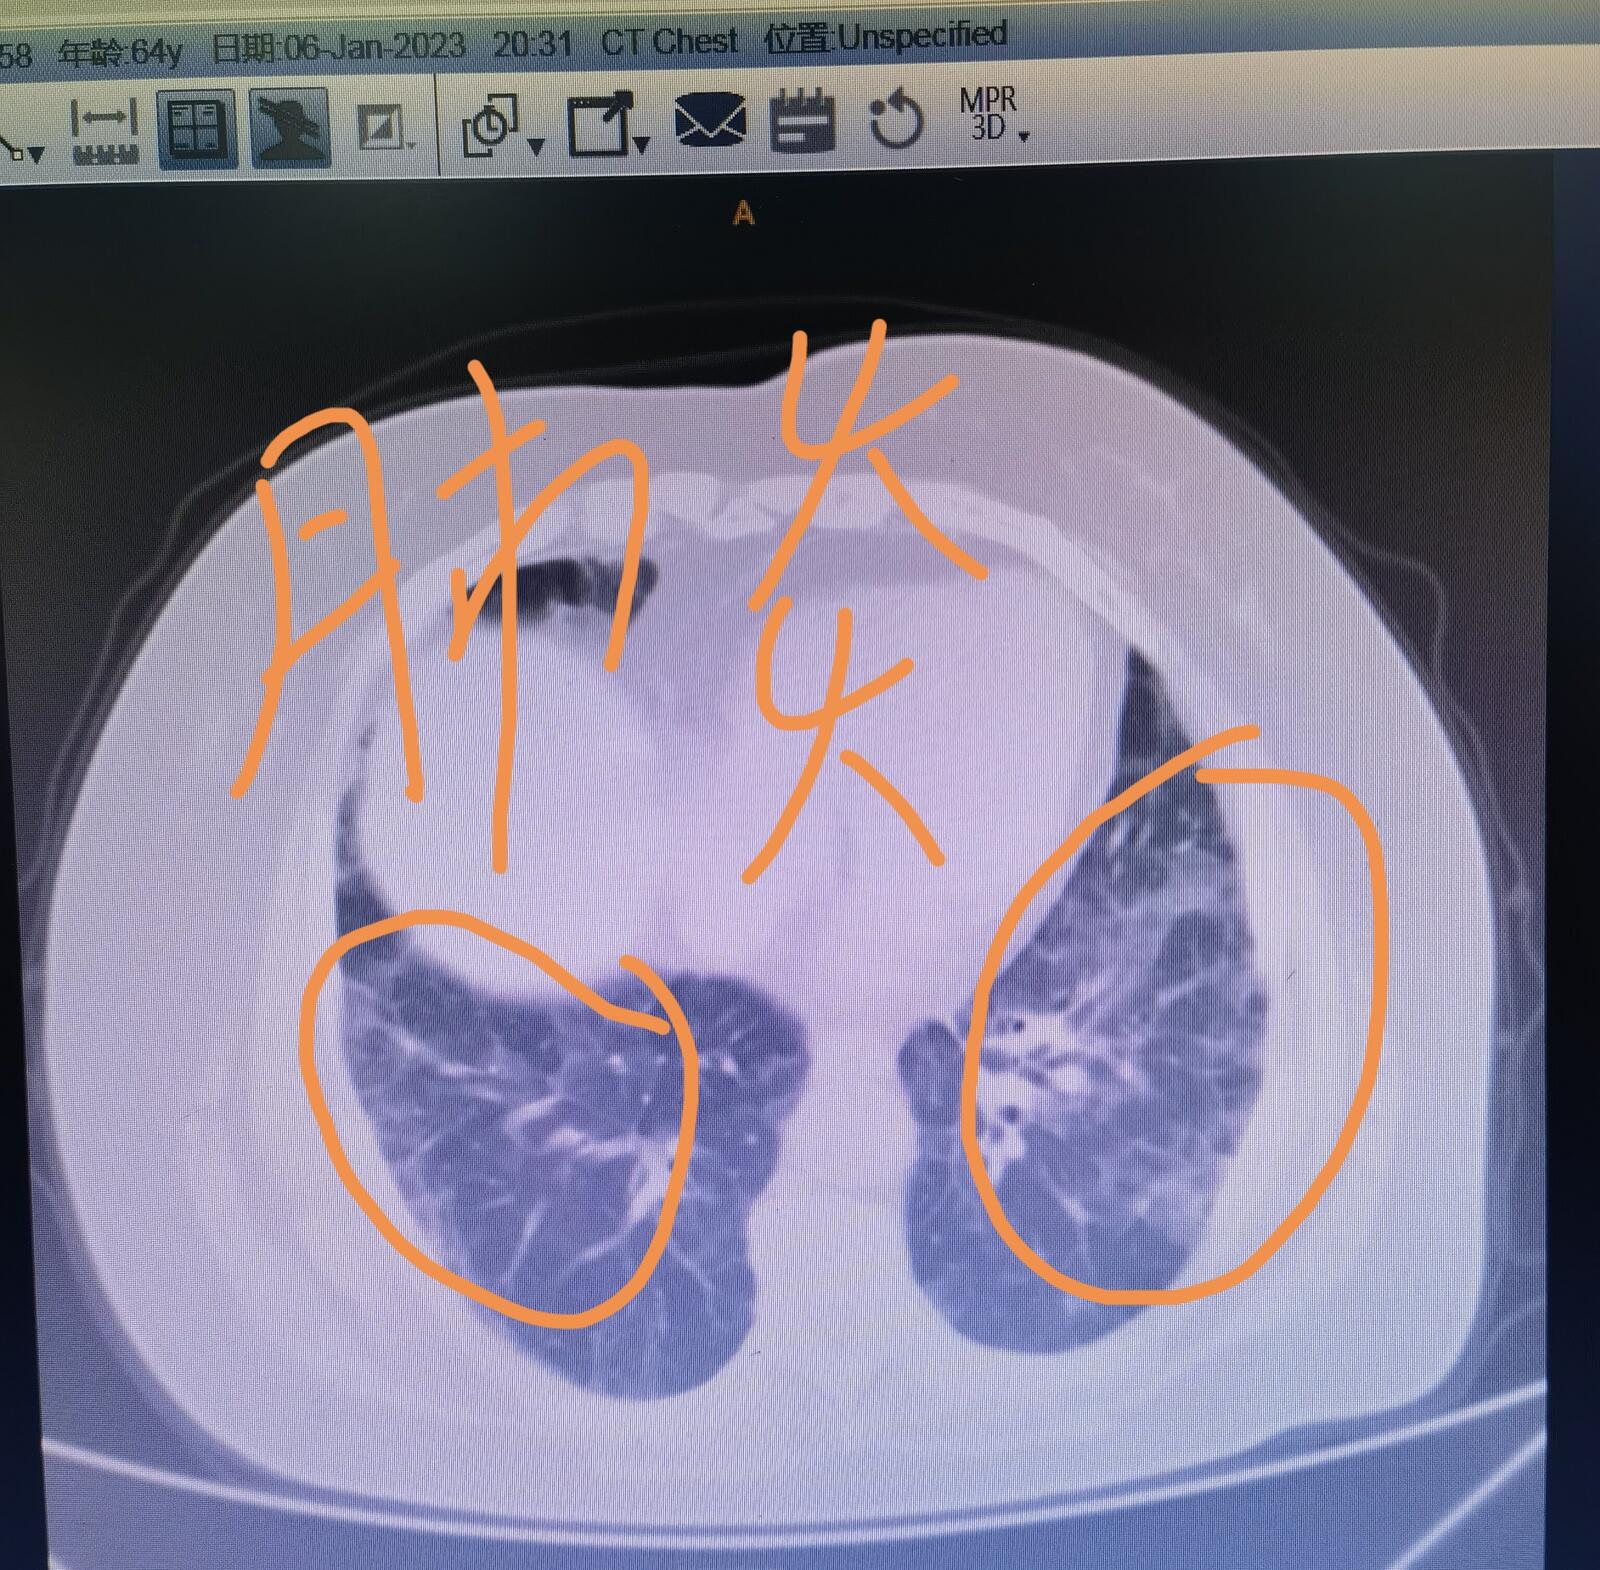

下面展示的这张CT片子,大家可以清楚的看到肺里面有这种磨玻璃的影像,很多朋友不知道磨玻璃影或者磨玻璃结节到底是什么样子,大家看看下面这张图就明白了,实际上就是大家家里面的浴室卫生间里经常用的不透明玻璃就叫磨玻璃。

这张片子是一位家住河北省唐山市的60多岁的女士的,三周之前她感染了新冠肺炎,当时她家里边其他家庭成员都发烧了,唯独她没有发烧,她做了抗原检测,发现是两道杠,那肯定是阳性了。过了几天,她觉得呼吸日渐困难,同时还伴有全身的疼痛,到家附近的县医院去治疗,治疗了一周,觉得症状没有缓解,又跑到天津来,到我们医院急诊来就诊,再一拍片子,肺里的感染比她在当地医院拍的有进展,需要安排住院治疗。